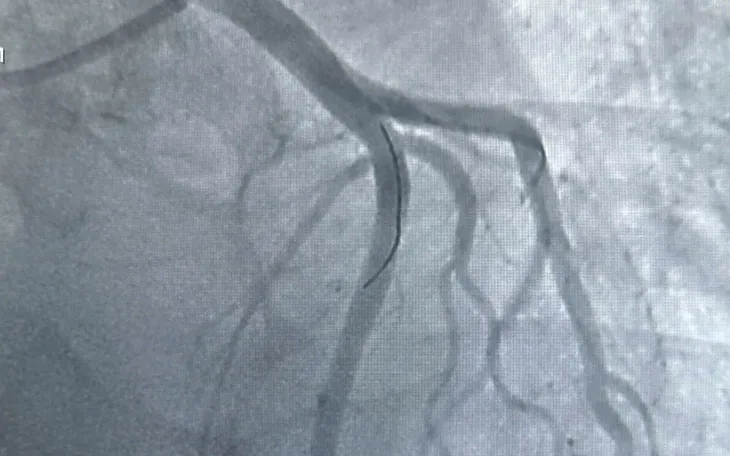

Một ca khác là bệnh nhân Đ.H.M. (55 tuổi) có nhiều bệnh nền, nhập viện muộn với nhồi máu cơ tim cấp vùng dưới. Kết quả DSA cho thấy mạch vành tổn thương cả ba nhánh, trong đó động mạch vành phải tắc hoàn toàn. Các bác sĩ đã đặt hai stent, cứu sống bệnh nhân trong tình huống nguy kịch.

Theo các chuyên gia, hệ thống chụp mạch số hóa xóa nền (DSA) giúp bác sĩ xác định chính xác vị trí tắc hẹp, từ đó can thiệp ngay tại chỗ, giảm biến chứng và rút ngắn thời gian điều trị. Bệnh viện Đa khoa Vĩnh Long hiện đã ứng dụng hiệu quả kỹ thuật này trong cấp cứu tim mạch, góp phần giảm tỷ lệ tử vong do nhồi máu cơ tim tại địa phương.